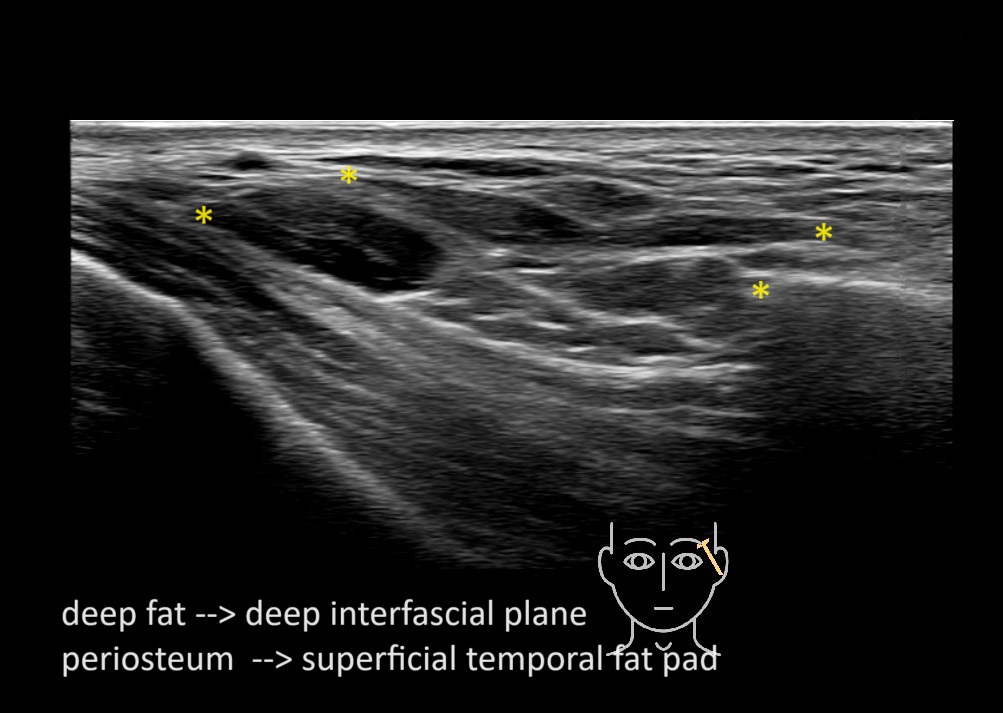

Filler behavior - Temple zygoma US

Study the first image to recognize the different layers. If you are sure about the layers, swipe to the second image to view the answer (if applicable).

Hover over an image to view the secondary image or click on the image title for more information.